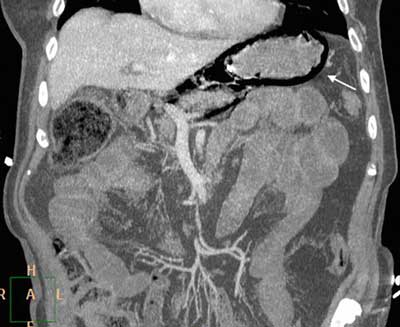

Figure 2

Contrast-enhanced CT, MPR reformats. Large amounts of intramural gas in the stomach (arrow) with no evidence of free peritoneal air.